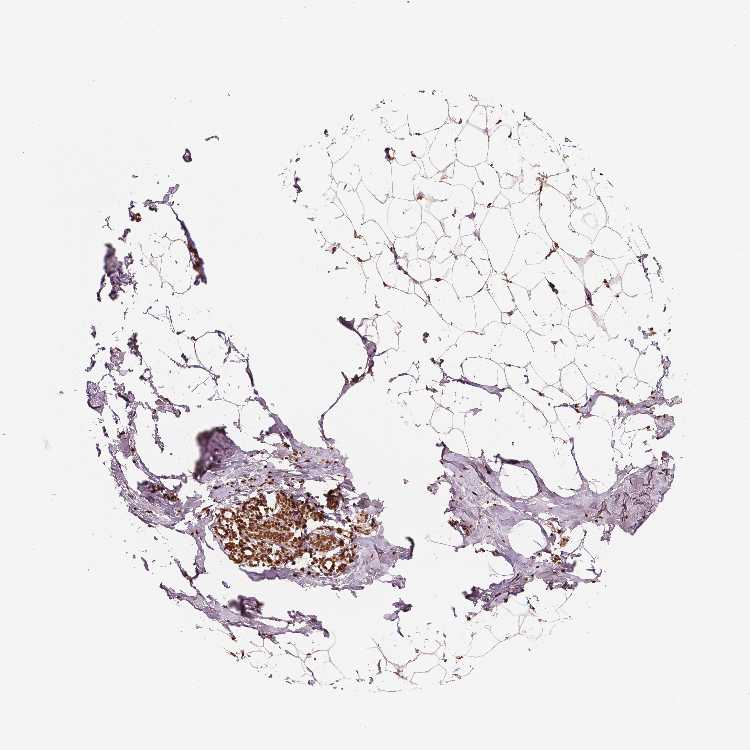

BREAST - Antibody stainingi

Antibody staining in the annotated cell types in the current human tissue is reported as not detected, low, medium, or high, based on conventional immunohistochemistry profiling in selected tissues. This score is based on the combination of the staining intensity and fraction of stained cells.

Each image is clickable and will lead to virtual microscopy that enables deeper exploration of all samples and also displays staining intensity scores, fraction scores and subcellular localization as well as patient and tissue information for each sample.

Antibody HPA042570Antibody CAB070190

Adipocytes HighHigh

Glandular cells HighHigh

Myoepithelial cells HighHigh